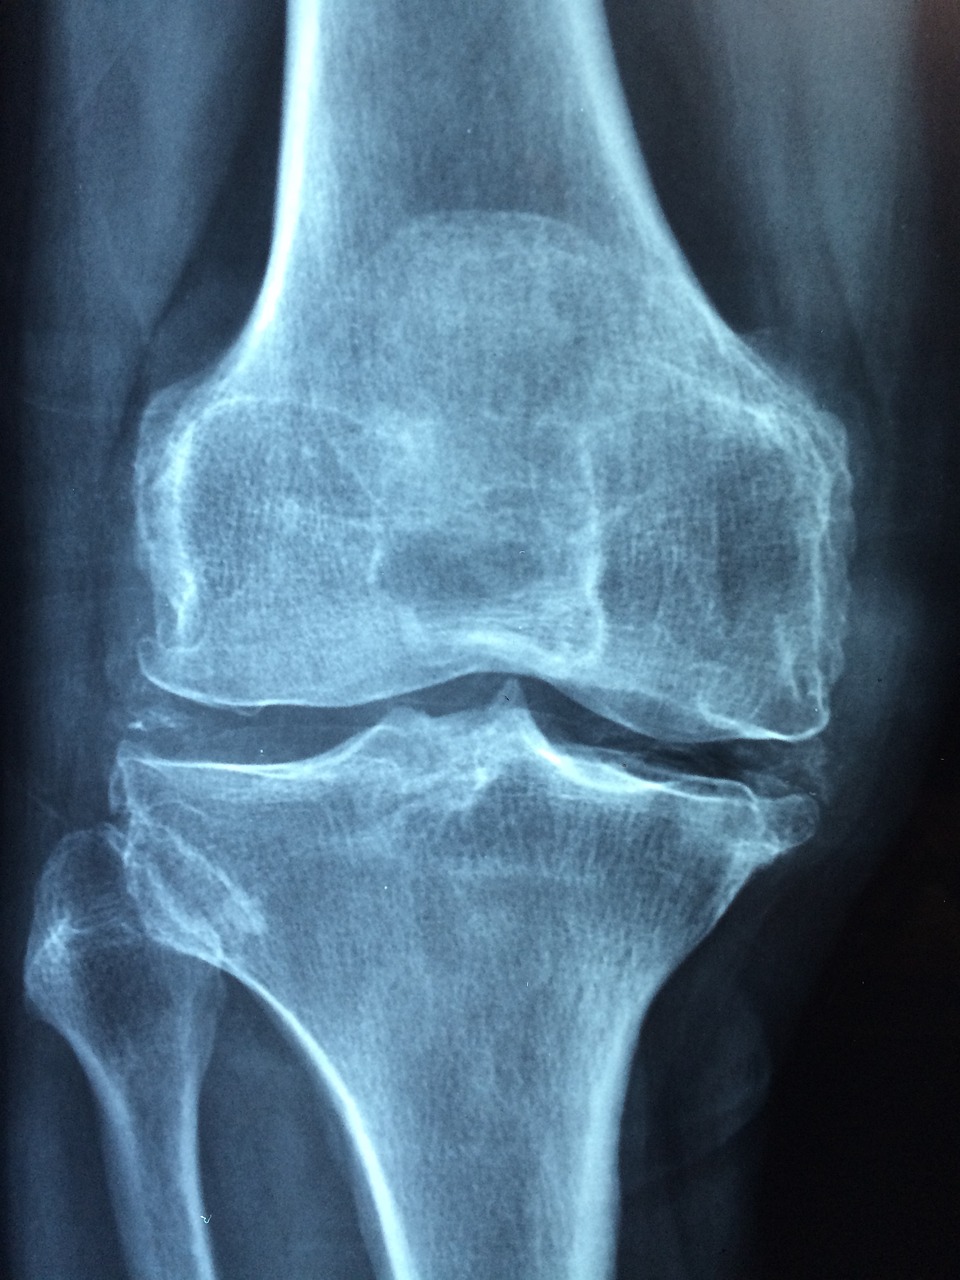

골다공증은 전 세계 수백만 명의 사람들, 특히 여성과 노인들에게 영향을 미치는 일반적인 질환입니다. 골다공증은 뼈를 약화시켜 뼈를 취약하게 만들고 골절되기 더 쉽도록 만듭니다. 골다공증의 원인, 증상 및 치료 방법을 이해하는 것은 예방과 관리에 매우 중요합니다.

골다공증이란 무엇인가요? 골다공증은 뼈의 질량이 낮아지고, 뼈조직이 악화되는 것을 특징으로 하는 진행성 뼈 질환으로, 뼈의 취약성과 골절에 대한 취약성을 증가시킵니다. 골다공증의 영향을 받는 뼈는 유해하고 약해져, 실제로 경미한 연쇄 작용이나 외상을 잠재적으로 위험하게 만듭니다.

골다공증의 진단 방법

- 골밀도 검사(DXA Scan): 이 비침습적 검사는 엉덩이, 척추 등 다양한 부위의 골밀도를 측정하여 뼈 건강을 평가하고 골다공증을 진단합니다.

- FRAX® 도구: 골절 위험 평가 도구는 임상적 위험 요인과 골밀도를 기준으로 개인의 골다공증성 골절 위험을 계산합니다.